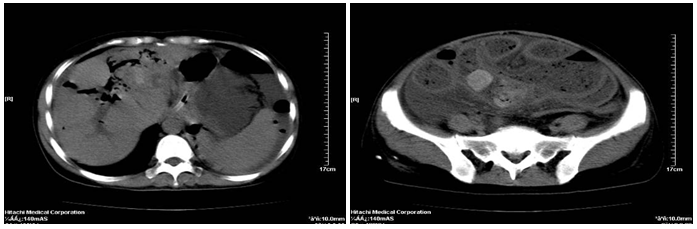

On physical examination, the female patient was found to have a distended, painful abdomen and weak bowel sounds with two operation scars at the right upper quadrant abdomen. She was afebrile and had a blood pressure of 100/70 mmHg, The Computed Tomography scan in our hospital demonstrated ileus with abdominal intestinal canal obviously effusion plot gas, intrahepatic bile ducts dilation and pneumobilia, hepatolithiasis, seroperitoneum, intestinal wall edema, with the possibility of stone obstruction in the small intestine(Figure 1). The gastrointestinal radiography using iohexol demonstrated duodenal diverticulum, intrahepatic bile ducts pneumobilia and ileus. On laparotomy, two large (3cm) gallstones were identified obstructing the distal ileum and two perforations of size 7-8 mm and 2-3mm respectively with approximately 1meter of gangrenous patches in the adjacent bowel (Figure 3). The ileum 20 cm from the ileocecal junction twisted for 540°C (Figure 2). Resection anastomosis was done. The patient is recouping well postoperatively.

Figure 2 Intraoperative picture showing the ileum of 20cm from the ileocecal junction volvulus of 540°C.

Figure 3 Intraoperative picture showing two large (3cm) gallstones obstructing the distal ileum and two perforations of size 7-8 mm and 2-3mm respectively.